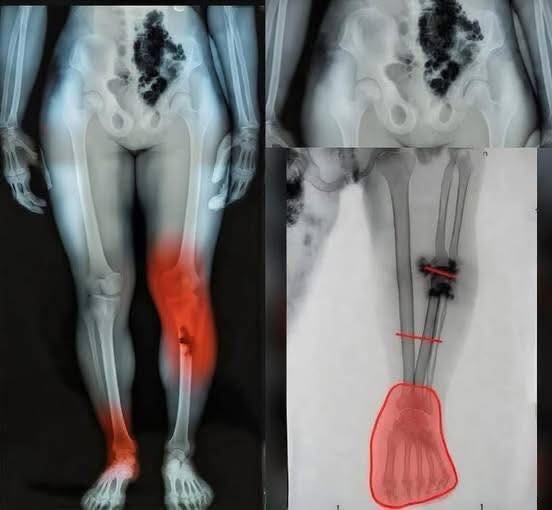

Medical professionals began looking deeper, trying to understand whether these cases were isolated or part of a broader trend. Some patients described a burning sensation, others a deep ache that seemed to come and go without warning. While not everyone experienced it, the consistency in certain reports was enough to raise concern and prompt further investigation.

Experts emphasize that the human body can respond in complex ways after illness, especially when the immune system has been heavily activated. In some cases, inflammation can linger or affect areas that weren’t initially involved. That doesn’t necessarily mean something dangerous is happening, but it does highlight how much researchers are still learning about long-term effects.